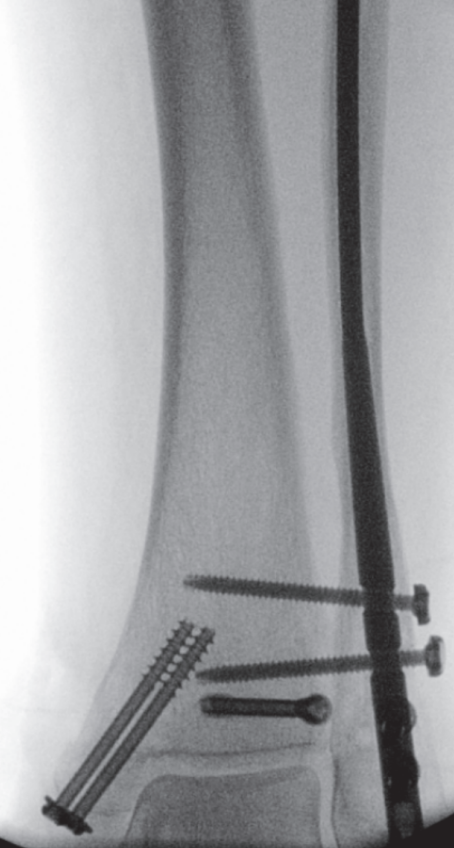

手术技术始于自腓骨尖向远端作短切口。锐性分离皮下组织,置入保护套筒。经套筒将导针置入髓腔并进入近端骨块。用空心开口器开髓,随后依次使用6.1毫米(远端)及3.1毫米、3.6毫米(近端)的钻头进行髓腔扩髓。扩髓过程在透视监控下进行,以避免皮质穿孔并确保钉道居中。将安装于瞄准器的腓骨髓内钉在透视引导下插入至预定深度,向外侧旋转,并用两枚前后向螺钉及两枚三皮质下胫腓联合螺钉锁定。未使用尾帽。最后于多平面进行透视记录(图5a–c)。彻底冲洗并止血后,将胫骨后肌腱复位,修复支持带,采用间断Donati缝合法分层闭合切口。敷以无菌敷料并用背侧夹板固定。

image.png

(a)

(b)

(c)

图 5. (a–c):最终术中透视图像:(a) 前后位视图,(b) 侧位视图,(c) 踝穴位视图。